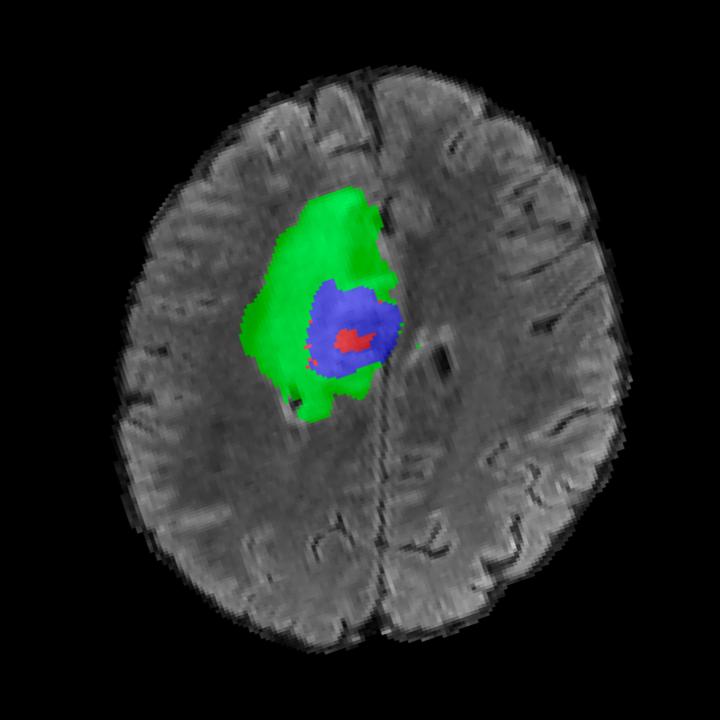

We conducted our experiments on two primary datasets for evaluations (BRATS & UK BioBank) and on two secondary datasets for out-of-domain generalization (IXI & fast knee MRI). BRATS is the largest public dataset of brain tumours consisting of 5,880 MRI scans from 1,470 brain diffuse glioma patients, and corresponding annotations of tumours [3, 42, 4]. All scans were skull-stripped and resampled to 1 mm isotropic resolution. All images have a resolution of 240 240 155, and we use the flair T2 sequence. Tumours are annotated for 3 classes: Whole Tumour (WT), Tumour Core (TC), and Enhanced Tumour Core (ET). UK Biobank is a more comprehensive dataset of 48,384 full-body MRIs from more than 500,000 volunteers[67], capturing diverse physiological attributes across a broad demographic spectrum. IXI is a dataset of T1-weighted 1.5 Tesla brain MRI images of 582 healthy subjects, freely available online [1]. Knee fastMRI is a public dataset of raw k-space data from NYU Langone[33, 80]. We use the test set provided (n=109) of fastMRI single coil, dimensions 640x372x30. These are center-cropped to 320x320x30.

Tumour Information Preservation. For the brain tumor segmentation, we use a Swin UNETR model[27, 70], trained with random rotation, and intensity as data augmentation. In Figure 5, we highlight the tumor profiles of the generated MRIs compared to the ground truth tumour profile. In the test set with human ground-truth annotations (), the real MRI Dice score is 85.15 while the generated MRIs from a single slice have a dice score of 83.09. This shows how the generated MRIs indeed preserve the tumor information and can act as an affordable and informative pseudo-MRI, before conducting an actual costly MRI examination in hospitals.

B.4 Tumour Information Preservation

On the test set with human ground-truth annotations (), the brain volumes generated from single slice input preserve the volume of the different tumour components (paired t-test, for all 3 classes) (see Table 3). The real MRI Dice scores are put for reference to our generated MRIs. X-Diffusion outperforms baselines TPDM [36] and ScoreMRI [18] in tumour preservation (see Table 3 and Figure 12). We ran experiments comparing the tumour segmentation Dice Score varying X-Diffusion configurations. The multi-slice input X-Diffusion achieves a marginally better Dice Score than the single-slice input model (83.47 83.09). We also ran experiments with slice input used for volume reconstruction intersecting or not with tumour. We observe on average a drop of 6% Dice Score (see Table 3). Further away from the tumour the input slice for volume reconstruction is selected, and we observe a linear decrease in tumour segmentation Dice Score with the lowest value of 77.21 Dice Score (see Figure 15).

| Test Dice Score | |||||

|---|---|---|---|---|---|

| X-Diffusion Generated MRIs | ET | WT | TC | Average Dice | 3D PSNR(dB) |

| single slice | 75.48 | 89.24 | 84.57 | 83.09 | 35.81 |

| multi-slice | 75.82 | 89.56 | 85.04 | 83.47 | 36.13 |

| multi-slice (only-tumour) | 76.12 | 90.04 | 85.87 | 84.01 | 36.98 |

| multi-slice (no-tumour) | 70.14 | 84.29 | 81.65 | 78.69 | 33.24 |

| Real | 76.47 | 91.13 | 86.24 | 85.15 | N/A |